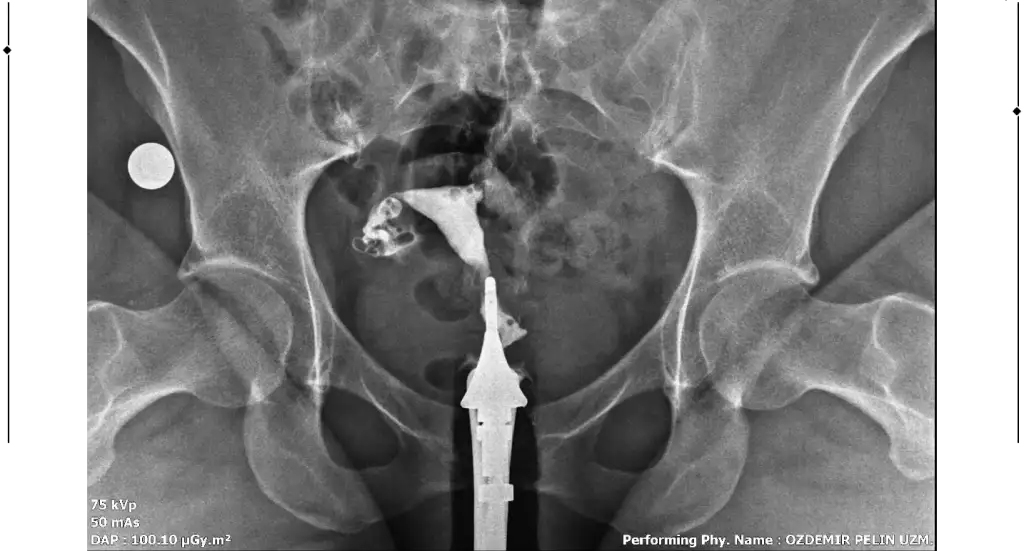

Merhaba, sağlıklı rahim gorseli ile kiyaslaninca sanki üstten biraz basık ama endişelenmeyin benim direk Y di belki çekim açısından olabilir, sizde sadece tüpleri anlayamadim dağılmış sanki açık tikaniklikda yok gibiMerhaba benim rahim filmim bu şekilde bir rapor oluşturulmadı filmi bugün çekildim doktora da gosteremedim. Yorumlanabilir misiniz?

Çok teşekkür ederim cevabınız içinMerhaba, sağlıklı rahim gorseli ile kiyaslaninca sanki üstten biraz basık ama endişelenmeyin benim direk Y di belki çekim açısından olabilir, sizde sadece tüpleri anlayamadim dağılmış sanki açık tikaniklikda yok gibi

Sizin yorumunuzu görünce bende hidrospenks baktım da sanki sağ tarafta boğum var gibi ama tek tüple de gebelik oluşuyor zaten benimde tıkalı malesef, yinede endişelenmeyin sakın korkuyorumda yorum yaparken yanlış anlaşılırim üzerim diyeGenişleme olabileceği söylendi yani sıvı olabilir dendi. Hidrosalpenks oluyor o var gibi geldi sanki bana

Anlayışınız için çok teşekkür ederim. Bakalım doktora gösterince net sonucu öğrenirim. Çok teşekkür ederim tekrardan.Sizin yorumunuzu görünce bende hidrospenks baktım da sanki sağ tarafta boğum var gibi ama tek tüple de gebelik oluşuyor zaten benimde tıkalı malesef, yinede endişelenmeyin sakın korkuyorumda yorum yaparken yanlış anlaşılırim üzerim diye

Ben de geçen hafta çektirdim HSG filmi. Raporum bugün oluştu ama anladığım kadarıyla sağ tüp açık sol tüp kapalı sanırım. Bana da yorumlama konusunda yardımcı olabilir misiniz? 4 senelik evliyim ve bebek sahibi olamadık, gebelik de hiç oluşmadı. Pcos'tan mustaribim. Tavsiyelerinizi alabilirim.

Merhaba bana da hidroselpenks gibi geldi çok hafif boğum var doktorunuzun yorumu ne oldu acabaMerhaba benim rahim filmim bu şekilde bir rapor oluşturulmadı filmi bugün çekildim doktora da gosteremedim. Yorumlanabilir misiniz?

Canım rahim yapısı güzelmişT tubiikk Ekledim görüntüleri, teşekkür ederim.

Sağ tüpün açık sol tüpün kapalıymış ben öyle anladım görüntüde de biri kapalı gözüküyor zaten